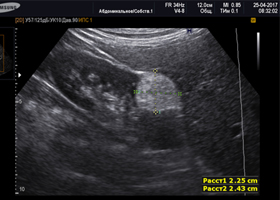

Анализы и диагностика

Диагностика опухолей почки в основном основывается на результатах ультразвукового исследования (УЗИ), рентгеновской компьютерной томографии (КТ) и магнитно-резонансной томографии (МРТ). При необходимости также выполняется биопсия, а также лабораторные анализы, такие как общий анализ мочи (ОАМ), общий анализ крови (ОАК) и биохимический анализ крови. Эти методы являются достаточно информативными и позволяют визуализировать опухоль, а также выявить характерный признак амилоидной опухоли — наличие жирового компонента в ее структуре. Для точной диагностики мелких амилоидных опухолей оптимальным решением являются методы лучевой диагностики, такие как мультиспиральная компьютерная томография (МСКТ), которые помогают определить размеры опухоли и отслеживать ее динамику.

На сегодняшний день установлен следующий алгоритм для динамического наблюдения: контроль размеров амилоидной опухоли с помощью УЗИ каждые три месяца, а также КТ с внутривенным контрастированием через шесть месяцев и через год.